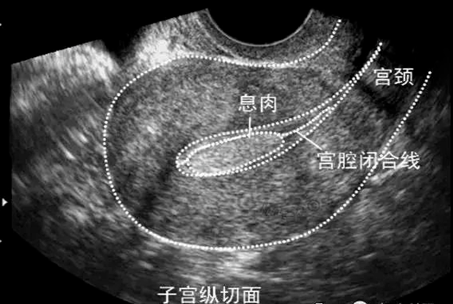

单发息肉典型超声表现为子宫肌层和内膜结构正常,宫腔内增强回声团,边缘连续光滑,外形规则,呈水滴状,在内膜较厚时,可见内膜形态不对称,息肉与正常内膜间界限清晰可辨,可见穿入性血流信号。

单发息肉典型超声表现为子宫肌层和内膜结构正常,宫腔内增强回声团,边缘连续光滑,外形规则,呈水滴状,在内膜较厚时,可见内膜形态不对称,息肉与正常内膜间界限清晰可辨,可见穿入性血流信号。